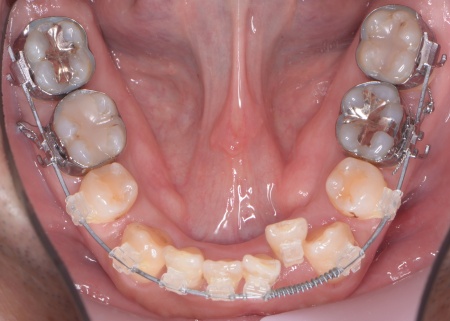

40代男性 乱れた歯並びと重度歯周病をワイヤー矯正と歯周再生療法で治療した症例

拝見したところ、上下の歯は、ずれたりねじれたりしてデコボコに生えており、著しく歯並びが乱れていました。

・上顎には歯の裏側に固定装置「トランスパラタルアーチ」を装着する

・下顎には小さな矯正用のネジ「ミニインプラント」を埋め込み、歯をしっかり動かすための支えにする

・歯の表面に小さなボタン状の装置であるブラケットを接着し、そこにワイヤーを通して歯を動かす「マルチブラケット矯正」を行う

まずは歯の移動スペースを確保するために、計6本の歯を抜きます。

その後、上下の歯の表面にブラケットを接着し、上顎にはトランスパラタルアーチを、下顎にはミニインプラントを使用しながら、マルチブラケット矯正を開始しました。